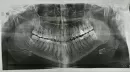

Определить данную патологию и подобрать плана лечения исходя из ортопантомограммы невозможно. Для этого необходим, как минимум, клинический осмотр. Вы должны понимать, если причинное оголения шейки зубов являются высоко прикреплённые тяжи соединительной ткани, то необходимо провести пластику преддверия полости рта до ортодонтического лечения. А необходимость гингивопластики определяют в ходе лечения.